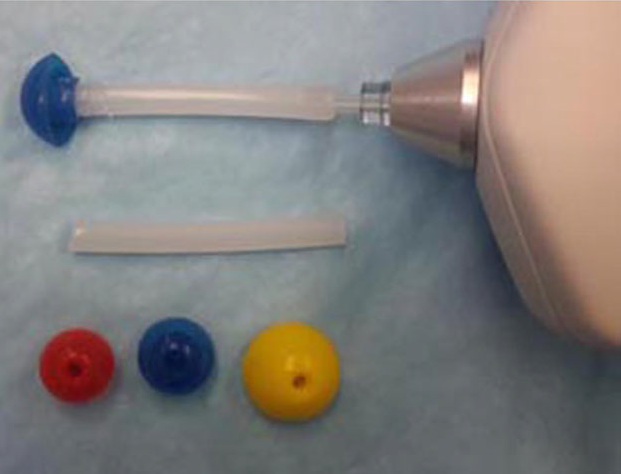

• middle ear

There

are two middle ears, the right one and the left one, each of which

consists of the ear drum, an air-filled

tympanic cavity, and three small bones (ossicles)

labelled the malleus, incus, and stapes, along with

their muscles and ligaments, and the tympanic membrane (eardrum).

(See the diagram at right.)

There

are two middle ears, the right one and the left one, each of which

consists of the ear drum, an air-filled

tympanic cavity, and three small bones (ossicles)

labelled the malleus, incus, and stapes, along with

their muscles and ligaments, and the tympanic membrane (eardrum).

(See the diagram at right.)

• tympanic cavity

The tympanic cavity (also called the middle ear cavity) is a rounded, hollow space behind the eardrum, (tympanic membrane) which is encased in the tympanic bulla, a thin, bubble-like bony vessel. It is within this cavity that the PSOM mucus is located. (See the "middle ear cavity" in the diagram above.) In cavaliers, this cavity has been found to be much smaller and flatter than the large, rounded cavity in other breeds.